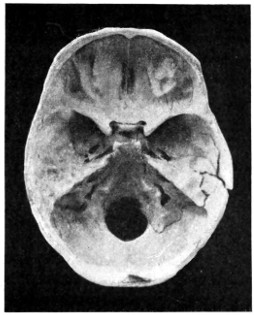

29 A and B. The base of the skull and the base as seen on transillumination 70, 71

30. Plan of the base of the skull 77